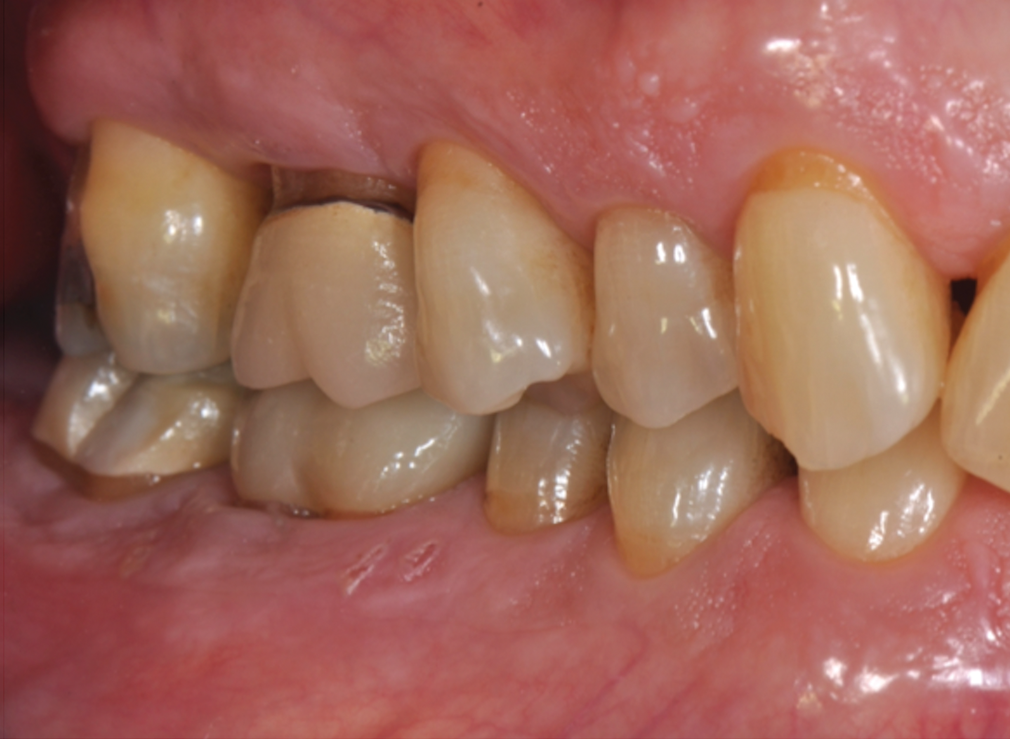

Fig 2. Pretreatment views: right lateral (Fig 2), frontal (Fig 3), and left lateral (Fig 4). Note: The maxillary right first molar (tooth No. 3) (Fig 2) would be identified as the most periodontally involved molar that was planned to be maintained.

Figure 2

Periodontal examination revealed generalized BOP and PDs up to 9 mm in the maxillary and mandibular molars with multiple furcations in each molar (Figure 2 through Figure 7). He presented with class I mobility in many posterior teeth and class II mobility in teeth Nos. 3 and 9 (maxillary right first molar and maxillary left central incisor, respectively). The periodontist decided to score tooth No. 3 for the PRS, as this was the most periodontally involved molar that was planned to be treated and maintained (Figure 2 and Figure 8). This tooth (maxillary right first molar = score 1) presented with probing depths of 7 mm (score 1); three total furcation invasions (score 3) (mesial [degree II furcation], buccal [degree I furcation], and distal [degree II furcation]); and a class II mobility (score 2). The total PRS for tooth No. 3 was 8, representing a "guarded" prognosis. Based on this score, the likelihood of not losing any teeth to periodontal disease for 15 years was 81%, and for 30 years the likelihood was just 56% (Figure 9).7